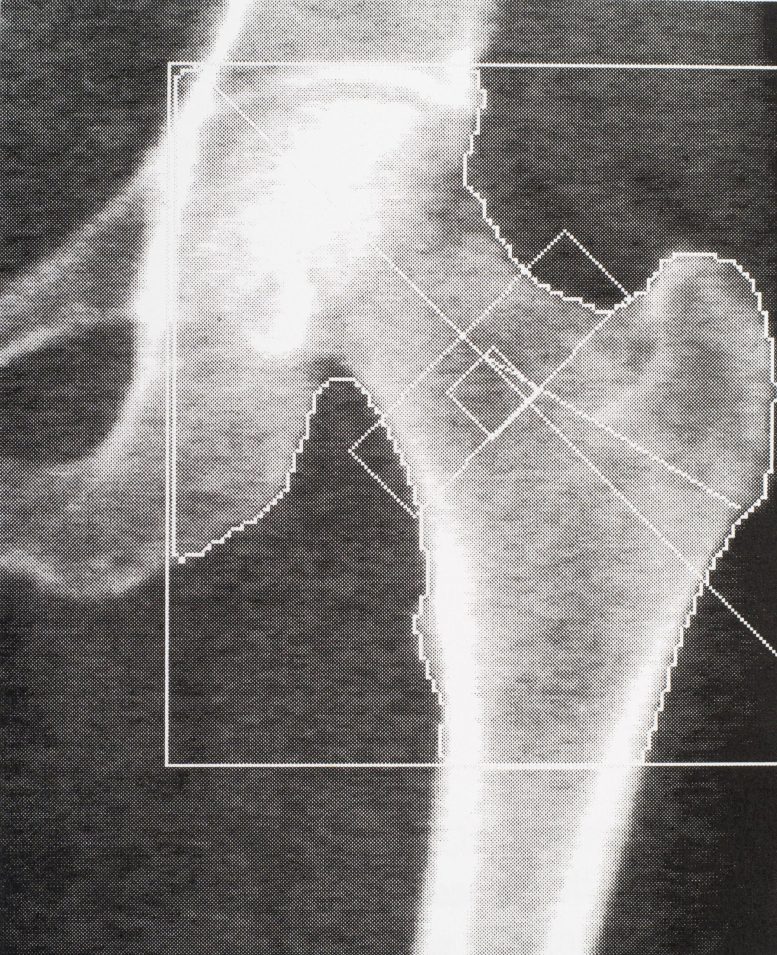

研究者はX線を調べて骨密度を特定しました。参加者は4〜5年ごとにインタビューを受け、骨スキャンや認知症のテストなどの身体検査を完了しました。